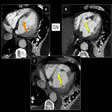

Ecocardiografía

Ésta muestra dilatación de la arteria pulmonar y del ventrículo derecho, así como movimiento anterior sistólico (paradójico) o aplanamiento si existe una sobrecarga de volumen significativa en el ventrículo derecho. El defecto puede visualizarse directamente en las ventanas subcostal, paraesternal derecha o apical. En la mayoría de los centros hospitalarios, la ecocardiografía bidimensional, complementada con examen con Doppler en color o convencional, ha sustituido al cateterismo cardíaco como prueba confirmadora de la existencia de una comunicación interauricular. La ecocardiografía transesofágica está indicada cuando el ecocardiograma transtorácico es ambiguo, como sucede a menudo con los defectos del seno venoso. El cateterismo se emplea si existen discrepancias con los datos clínicos, si se sospecha una hipertensión pulmonar significativa o malformaciones asociadas, o si existe la posibilidad de una enfermedad coronaria.